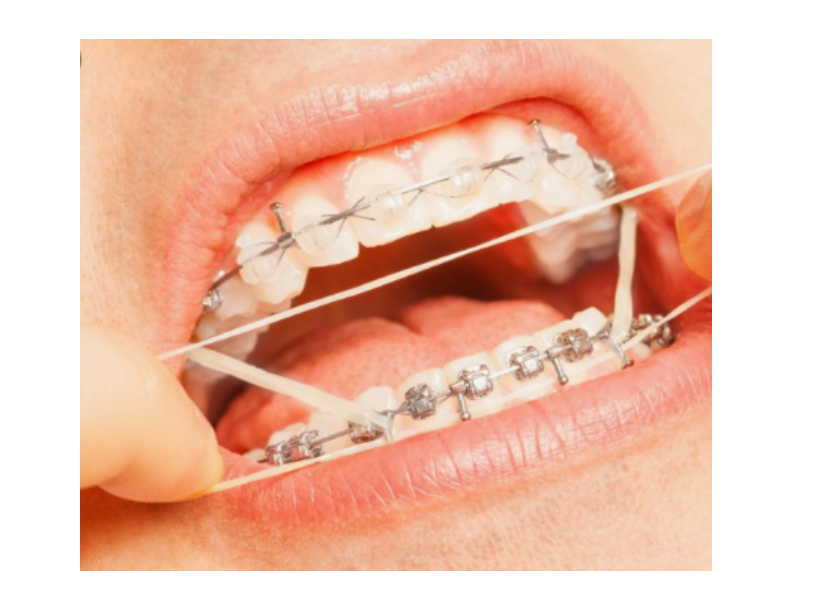

교정 마무리쯤에 고무줄을 끼는 이유는 중심선을 맞추기 위해서입니다!

치아 교정 마무리 즈음에

중심선을 맞추려고 노력하긴 하지만

교정으로 해결할 수 없는 경우도 분명히 있으니까요!!